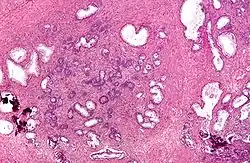

Micrograph showing nodular hyperplasia (left off center) of the prostate from a transurethral resection of the prostate (TURP). H&E stain. -

Microscopic examination of different types of prostate tissues (stained with immunohistochemical techniques): A. Normal (non-neoplastic) prostatic tissue (NNT). B. Benign prostatic hyperplasia. C. High-grade prostatic intraepithelial neoplasia. D. Prostatic adenocarcinoma (PCA).